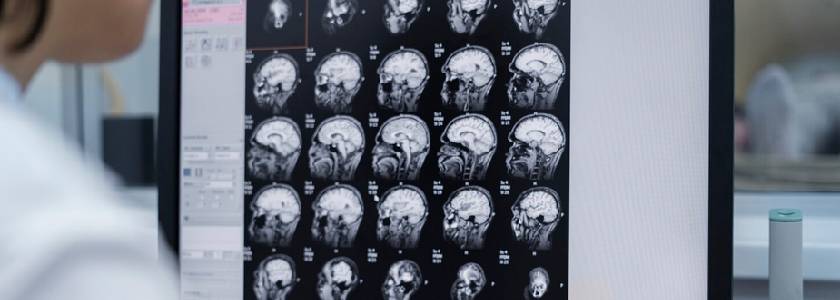

एक जिम्मेदार के रूप में हरियाणा में सिर की चोट का इलाज करने वाले डॉक्टर डॉ. सिंह अनावश्यक परीक्षणों से बचते हैं लेकिन सुरक्षा से कभी समझौता नहीं करते हैं। निदान नैदानिक परीक्षा और इमेजिंग पर आधारित है। यह भी शामिल है:

• मस्तिष्क का सीटी स्कैन

• आवश्यकता पड़ने पर एमआरआई